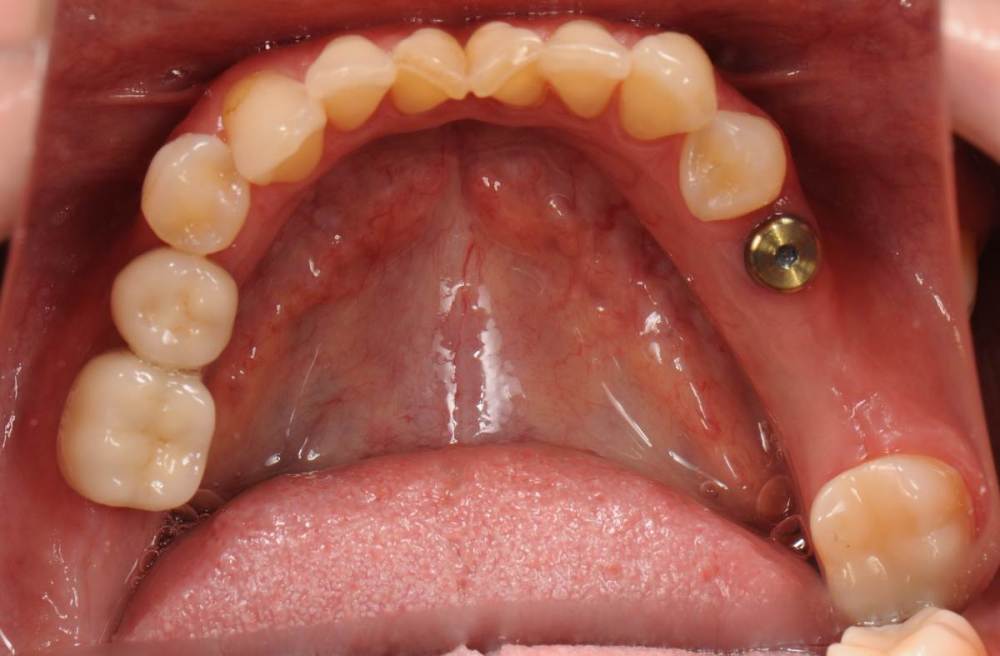

После ортодонтии и имплантации(делал не я):

21276649_.thumb.JPG.ac6bc70f88acb74ec8f69200429a4628.JPG

DSC_6448.thumb.JPG.8410ca5b1d184dbe575abfe993920475.JPG